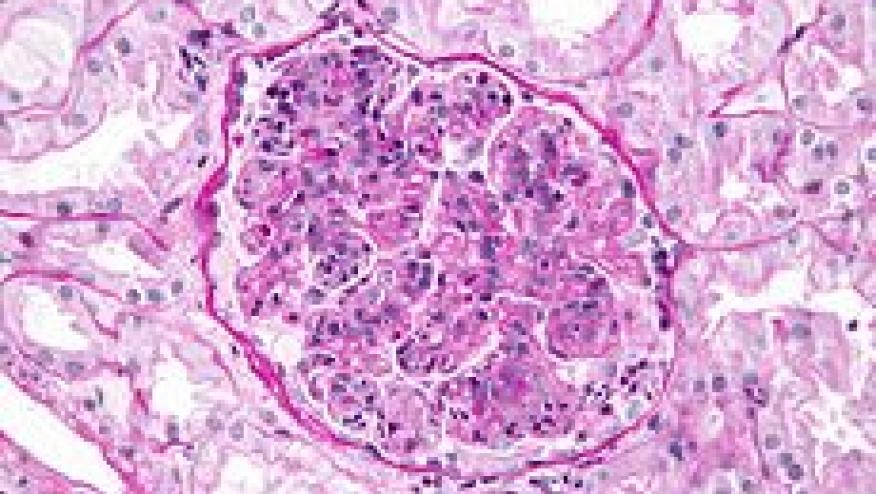

Tacrolimus Tops Other DMARDs as Induction Therapy for Lupus Nephritis Save

Metanalysis of nine clinical trials and 972 lupus patients examined the comparative efficacy of tacrolimus, mycophenolate (MMF) and cyclophosphamide (CYC) as induction therapy for lupus nephritis. Pairwise comparisons were performed, including 11 direct comparisons (Citation source http://buff.ly/1U1wchB).

The response rate with tacrolimus was significantly higher than with CYC (OR 2.35, 95% CI 1.03-5.45). The overall response rate was higher, though not statistically significantly so, with MMF compared with CYC (OR 1.45, 95% CI 0.96-2.42). Tacrolimus was most efficacious as induction treatment for patients with lupus nephritis, and had the highest probability of decreasing the risk of serious infections. Higher remission rates combined with a more favorable safety profile suggest that MMF is superior to CYC as induction treatment in these patients.